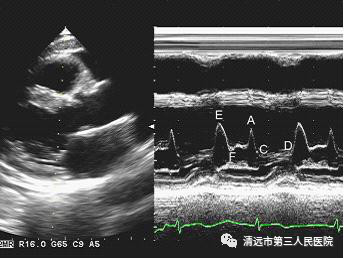

下面為心臟彩超檢查部分圖譜

正常左心室長軸M型超聲波形圖